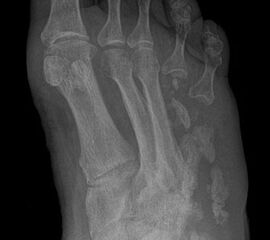

Wegen des Risikos einer Ulzeration am Metatarsalekopf (Abb. 14) sollte die Exartikulation im Grundgelenk vermieden werden. Günstiger ist es, falls möglich, einen kurzen Grundglied­stumpf als Platzhalter zu belassen (Abb. 15). Wenn Zehen in eine Lücke zu kippen drohen, kann die mit einem Platzhalter verhindert werden (Abb. 16, 17)

Die Zehe wird tennisschlägerartig umschnitten (Abb. 24). Falls ein infiziertes plantares Ulkus vorliegt, kann die Exzision dieses mit einbeziehen. Dies ist jedoch meistens nicht erforderlich. Das proximale Inzisionsende reicht bis an das TMT Gelenk. Das Metatarsale wird möglichst proximal osteotomiert, wobei am 1. Strahl eine Kantenbildung nach medial und 5. Strahl eine nach lateral vermieden werden muss. Es soll erreicht werden, dass die Nachbarzehen sich annähern, um das Kippen einzelner Zehen zu vermeiden (Abb. 25). Es wurde vorgeschlagen, die Fußverschmälerung durch einen Minifixateur, der zwischen 1. und 5. Mittelfußknochen angelegt wird, zu begünstigen (Bevilaqua 2013). In unserem Patientengut hat sich hierfür nie die Notwendigkeit ergeben, da sich die Mittelfußköpfe durch Narbenzug spontan annäherten und narbig stabil verheilten (Abb. 26). Bereits nach wenigen Wochen hat sich der Fuß verschmälert und bietet ein kosmetisch günstiges Ergebnis (Abb. 27).